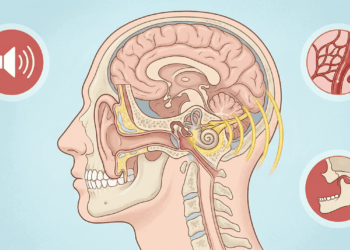

Nem toda tosse é igual, e o tipo que você apresenta pode revelar muito sobre o que está acontecendo no seu corpo. A tosse seca e persistente, por exemplo, costuma estar ligada a alergias respiratórias, asma, refluxo ou até ao uso de certos medicamentos para pressão alta. Já a tosse com catarro geralmente aponta para infecções como gripe, bronquite ou pneumonia.

Existe ainda a tosse noturna, que piora ao deitar, frequentemente associada ao refluxo ou ao gotejamento de secreção nasal na garganta. E a tosse que vem acompanhada de um som agudo, semelhante a um “guincho”, pode ser sinal de coqueluche, uma infecção bacteriana que voltou a preocupar autoridades de saúde em diversos países.

REFLUXO

O ácido do estômago pode subir até a garganta e causar tosse seca, piorando após refeições e à noite.

RINITE E SINUSITE

O muco que escorre pela garganta ativa constantemente o reflexo da tosse.

ASMA

Em alguns casos, a tosse seca persistente pode ser o único sintoma da asma.